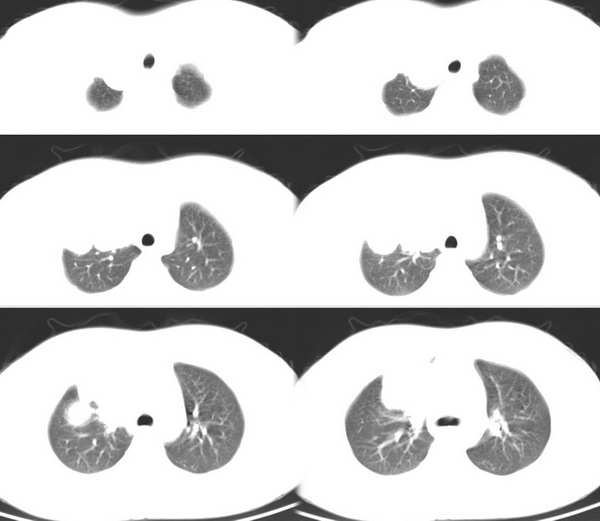

男,18岁。咳嗽,胸闷4天。

纵隔图像呢?metastasis.

肺转移